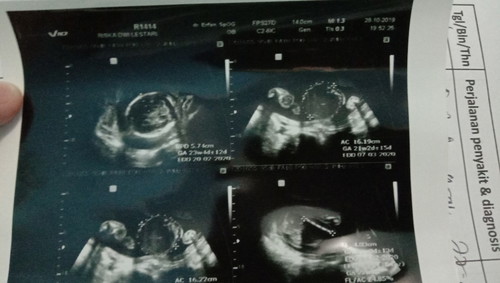

Assalamualaikum bunda" semua kemarin saya baru USG alhamdulillah semuanya bagus, cmn Jari" mungil nya belum terlalu kelihatan... Semoga bunda semua sllu diberi kesehatan sma dde bayinya ??